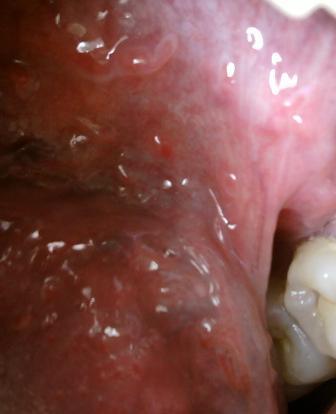

治疗尖锐湿疣的权威专科医院如果不及时进行治疗,随着时间的推移,病情就会逐渐加重,最终失去治疗的最佳时间。尖锐湿疣的主要发病人群集中在20岁到25岁之间的年轻人群。尖锐湿疣在初期表现为淡红色的小丘疹,表面凹凸不平,有的如菜花状,表面湿润,分泌物呈现灰白色,早发现早治疗是治疗尖锐湿疣应该坚持的基本原则。